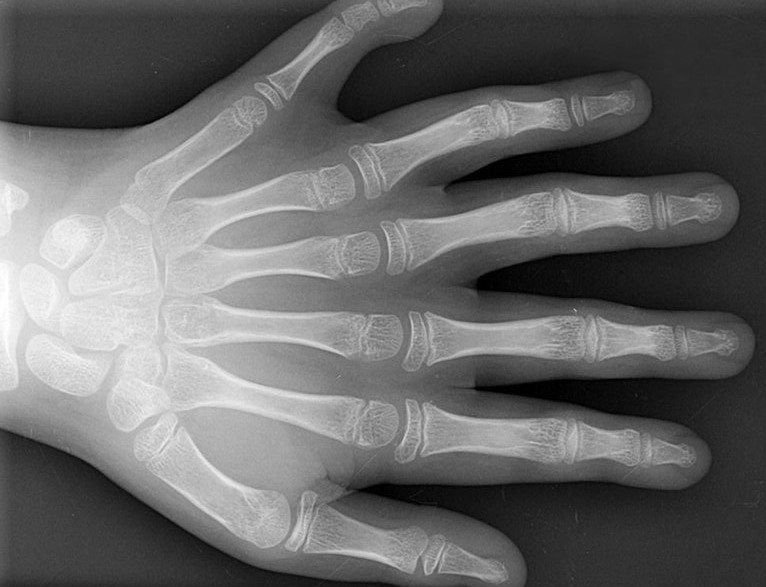

Polydaktýlia

Polydaktýlia je vrodená fyzická anomália určená evolučnou fázou štvornožcov, kedy sa pri premene plutiev v končatinách vyvinulo viac ako dnes bežných päť prstov. Z hľadiska súčasnej medicíny ide o súhrnné označenie vrodenej chyby, ktorá má za následok väčší počet prstov na nohe alebo ruke než je bežné. Polydaktýlia sa môže vyskytovať izolovane ako jediná ťažkosť pacienta, alebo môe byť súčasťou iných syndrómov, napr. Pattauov syndróm. Často býva táto chyba dedičná, teda môže byť frekventnejšia v niektorých rodinách - je to tak u familiárnej polydaktýlie. Najbežnejšou formou polydaktýlie u ľudí je šesťprstosť. Prsty navyše bývajú častokrát slabo vyvinuté, najčastejšie vyrastajú z malíčka. Niektoré sú aj funkčné. V prípade, že prebytočný prst / prsty nemajú kosti, môžu aj samé odpadnúť. Väčšie prsty bývajú chirurgicky odstraňované.

• viac ako päť prstov na ruke alebo nohe

• izolovane, ale aj ako súčasť iných syndrómov